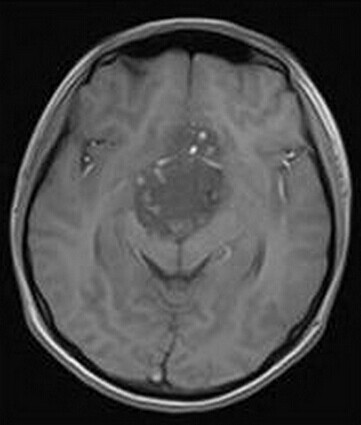

患者:男,15岁,双眼视力下降1年余,近来有嗜睡表现。

【正确答案】A 颅咽管瘤

(1)颅咽管瘤的两个发病高峰年龄分别是4-15岁和35-45岁,其中实性颅咽管瘤多见于成年人,本例为青少年患者,发病年龄无特异性;

(2)对诊断有提示意义的征象是明显强化,内散在微囊状不强化区。